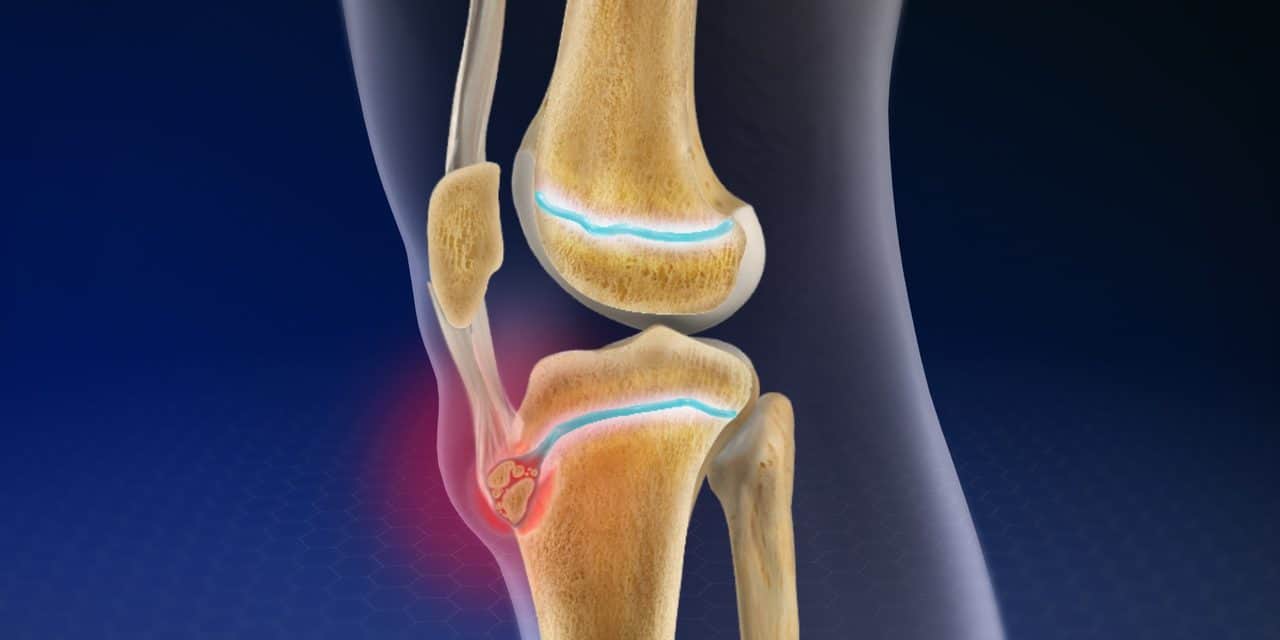

Meniscal Injury

Knee Osteoarthritis